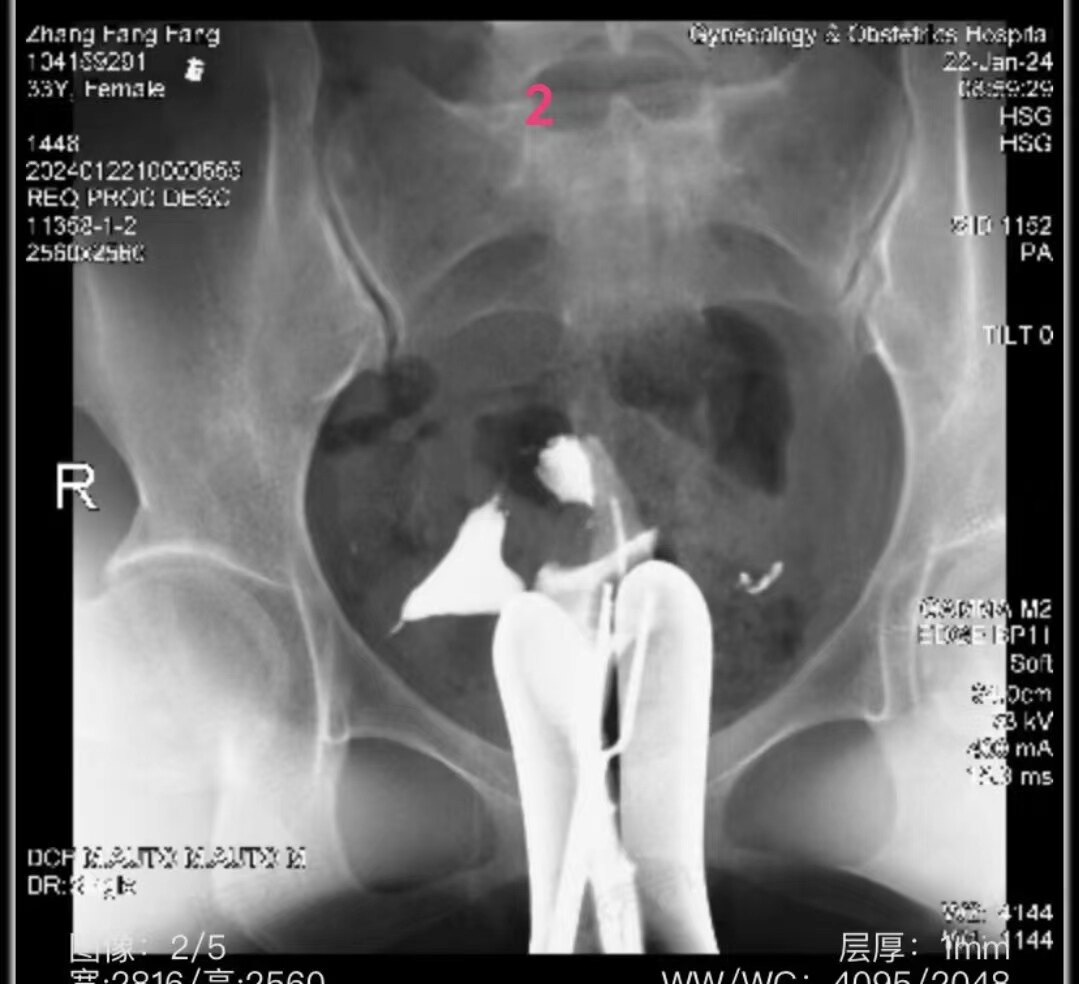

左侧输卵管显影至壶腹部,右侧输卵管显影至峡部。造影剂返回到阴道

2.jpg